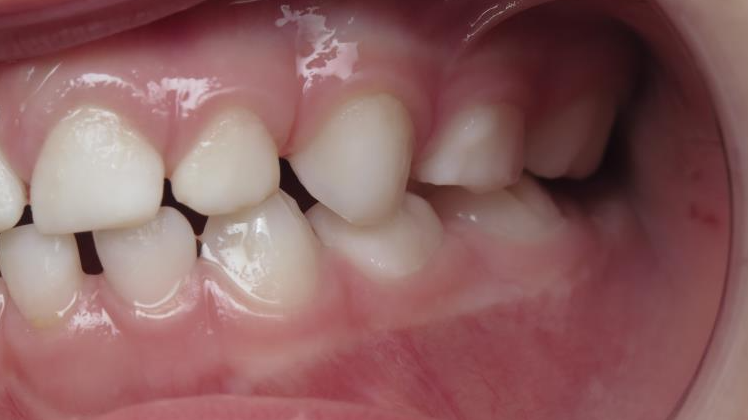

7.inversé droit 4 ans

inversion des dents postérieur coté droit